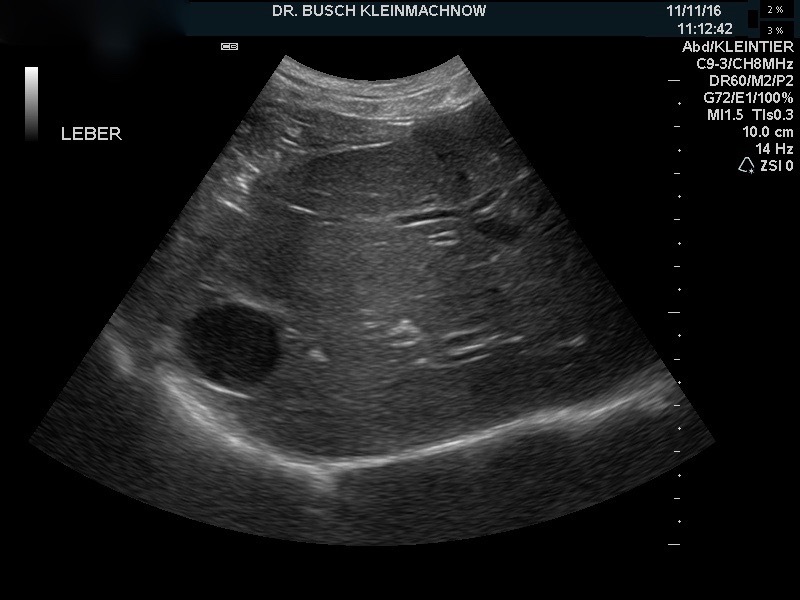

Ja, Bobby ging es sichtlich schlecht, so matt er auf meinem Behandlungstisch herumlag, ohne Interesse an Leckerlis oder anderen Dingen. In seinen Därmen rumorte es, sein Magen gluckerte, und bei dem Abtasten des Abdomens zeigte er deutliche Bauchschmerzen. Die mitgebrachte Kotprobe war dünnflüssig, mit Schleim und Blut überzogen und stank fürchterlich. Um Bobby zu helfen, musste ich erst einmal herausfinden, wie ernst die Lage war. War er schon dehydriert? Hatte er möglicherweise doch einen Fremdkörper aufgenommen? Oder waren Parasiten oder Giardien verantwortlich für den Durchfall?